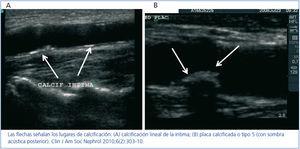

La ecografía carotídea es la única técnica que permite localizar el lugar que ocupa el calcio en la pared arterial. Nuestro grupo ha llevado a cabo un estudio para analizar este aspecto mediante ecografía de arterias carótidas y femorales, utilizando como control la arteria braquial por ser un territorio libre de ateromatosis29. Observamos que la calcificación se encontraba principalmente en la capa íntima, siguiendo dos patrones: 1) calcificación de la placa ateromatosa (figura 2a), y 2) calcificación lineal de la íntima no relacionada anatómicamente con la placa ateromatosa (figura 2b). Esta localización, no descrita anteriormente, se asoció en el análisis multivariante con: edad, fósforo plasmático, proteína C reactiva y presencia de ateromatosis. Estos resultados ponen de manifiesto que en el sustrato de la calcificación de las arterias elásticas subyace la inflamación y la ateromatosis. Aunque el fósforo plasmático sigue siendo un «enemigo a batir», debemos prestar atención a la prevención de la ateromatosis y a disminuir en lo posible el estado proinflamatorio de la ERC.

Figura 2. Patrones de calcificación definidos por ecografía